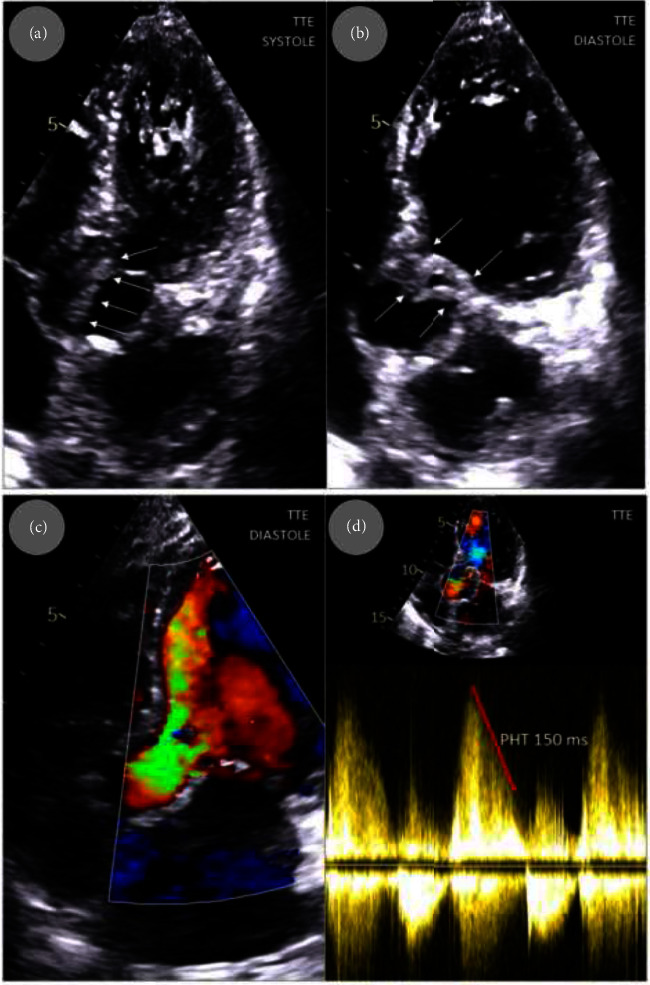

Introduction: Broviac catheter is a type of central venous catheter (CVC) used for long-term parenteral nutrition in specific patients, e.g., diagnosed with intestinal failure as short bowel syndrome (SBS). The way of the catheter insertion is conceived to minimalize the risk of infections. However, CVC-related blood stream infections (CVC-BSIs), including infective endocarditis (IE), remain most important complications associated with Broviac catheter. Staphylococcus epidermidis stands out as a prevalent pathogen. The increasing number of CVCs results in an increased incidence of healthcare-associated IE. Complete parenteral treatment is an independent risk that increases the likelihood of IE. Treatment of IE is mainly based on antibiotic therapy, but in certain cases, surgical treatment is needed. Presentation of Case: A 71-year-old female with SBS who had been receiving total parenteral nutrition through the Broviac catheter for several months was admitted in a serious condition with significant weakness, increasing shortness of breath, deteriorating cough, fever, low blood pressure, and heart palpitations. Echocardiography revealed severe aortic valve IE with a large, longitudinal, highly mobile vegetation (up to 40 mm) and massive aortic regurgitation with pulmonary edema. Fast pathogen detection in the patients' blood (S. epidermidis) was obtained using PCR-based multiplex test. Due to life-threatening conditions, emergency surgery with aortic valve replacement was performed. Consistent rehabilitation resulted in good condition achievement. Follow-up echocardiography showed normal function of the aortic valve bioprosthesis. Conclusion: The use of CVC, including Broviac catheter, is associated with an increased risk of infections, including IE. Treatment-resistant severe HF complicating IE requires emergency surgery.